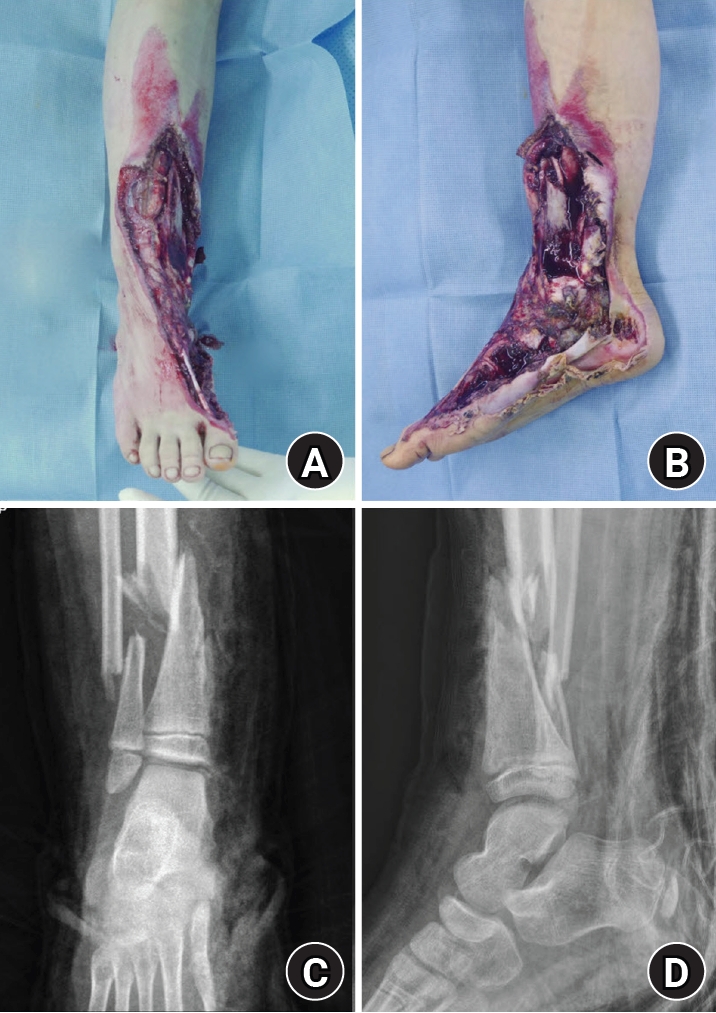

An 8-year-old girl presented after a traffic accident with a severe crush and degloving injury of the medial right ankle and foot, a distal tibiofibular fracture, and medial midfoot bone defects. After staged irrigation and debridement with temporary external fixation, definitive reconstruction was performed on August 6, 2016. The medial malleolar defect (2.5×2.0 cm) was reconstructed using a contoured autologous iliac crest bone graft secured with internal fixation, and medial stability was augmented using harvested gluteal fascia as a deltoid ligament substitute fixed with suture anchors. A bone-cement spacer was placed adjacent to the injured physis to mitigate physeal bridging, and the extensive soft-tissue defect was covered with a free anterolateral thigh flap and skin graft. During follow-up, progressive varus deformity and contracture were managed with corrective osteotomy and plating, Achilles tendon lengthening, Z-plasty, and Ilizarov fixation. At the final follow-up (March 6, 2025), the limb-length discrepancy was 5 mm, active ankle dorsiflexion was 0° (passive dorsiflexion 5°), and the patient was pain-free with full participation in daily activities, including hiking and dancing. This case emphasizes the value of an integrated staged strategy that combines bony reconstruction, medial stabilization, physeal management, and durable soft-tissue coverage during skeletal growth.